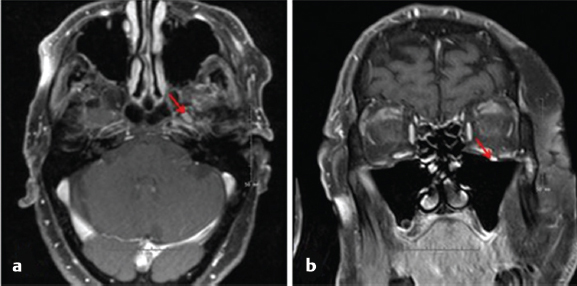

7 Role of Radiotherapy in the Treatment of Skin Malignancies Non-melanomatous skin cancers (NMSC), specifically basal cell carcinoma (BCC) and squamous cell carcinoma (SCC), are the most common malignancies in the United States. They are primarily managed surgically and carry an excellent prognosis, with a 1 to 5% rate of disease recurrence after complete excision and only exceedingly rare instances of distant metastasis. Historically, radiotherapy played a prominent role in the definitive management of these cancers as an alternative to surgical resection, especially in cosmetically sensitive areas. With the improvement in surgical techniques in recent decades, especially the widespread use of Mohs micrographic surgery (MMS), the use of curative radiation for skin cancers has declined. However, radiation is still commonly used in the definitive setting for patients with NMSC who are poor surgical candidates or have larger lesions in cosmetically sensitive regions of the face, and in the postoperative setting for more advanced tumors that have high-risk pathologic features that are associated with excessive risks of locoregional recurrence after surgery alone. Radiotherapy plays a similar role in the postoperative management of cutaneous melanoma. Radiation also offers excellent palliation for noncurable patients. This chapter reviews common indications, dose and fractionation schedules, techniques, and oncologic and cosmetic outcomes for radiotherapy for NMSC and melanoma ( Both surgery and RT can offer excellent cure rates for the management of early-stage NMSC. Surgery is typically the preferred method of treatment, given it can be performed in a single session, and has been associated with superior oncologic and cosmetic outcomes. One prospective randomized study compared the outcomes of MMS and definitive RT in 347 patients with less than 4 cm BCC of the face. The local failure rate was 0.7% for patients treated with MMS and 7.5% for patients treated with RT. Additionally, the cosmetic outcome was rated “good” or better more often in those patients who underwent surgery (87 vs. 69%).1 Though the technique of RT was not controlled (55% received interstitial brachytherapy and 45% received orthovoltage therapy), which could have affected the quality of the comparison, as the only randomized study, this trial remains pivotal in guiding medical decision making. A variety of factors can influence the decision to favor RT rather than surgery for NMSC. Typical contraindications to definitive RT include very large tumors and those with bone and/or cartilage invasion, given that control rates are typically inferior, as well as recurrent tumors that have been previously radiated or arise in an area of previous radiotherapy. Radiation should also be avoided in patients with genetic radiosensitivity syndromes, such as xeroderma pigmentosum and basal cell nevus syndrome, and in those with active connective tissue diseases, such as scleroderma and systemic lupus erythematosus.2 Patients who are candidates for definitive RT include those with unresectable disease, older patients with comorbidities limiting their surgical options, and patients with lesions involving the eyelid, canthi of the eye (especially those who carry surgical risk to the lacrimal duct), external ear ( Fig. 7.1 A modern linear accelerator, capable of delivering photon and electron radiotherapy with image guidance provided by cone beam CT (red arrow). A robust literature, much of it older when RT was more commonly used, supports the safety and efficacy of definitive RT for many of these aforementioned types of patients. A review of 986 BCC and SCC of the skin overlying the eyelid treated with definitive RT demonstrated a 5-year cure rate of 96.4%.3 A review of 334 BCC and SCC of the external ear at the Princess Margaret Hospital treated with definitive RT demonstrated a 2-year local control rate of 87%, with severe late toxicity noted in only 7% of patients.4 A review of 100 patients with SCC of the nasal skin at the Princess Margaret Hospital treated with definitive RT demonstrated a 2-year local control rate of 90%, with no severe toxicities observed.5 Fig. 7.2 (a) SCC of the helix of the left ear with bleeding (baseline). (b) After treatment with definitive radiation therapy (50 Gy in 20 fractions with electrons). There was complete remission with excellent cosmesis. Fig. 7.3 (a) A 96-year-old patient with right retroauricular BCC, T2N0M0 (baseline). (b) One month after treatment with definitive radiation therapy (50 Gy in 20 fractions with electrons). While definitive RT monotherapy can provide effective tumor control for T1–3N0 NMSC, T4 tumors and those with nodal metastases demonstrate inferior outcomes. Initial surgical management is recommended in these patients, often followed by adjuvant radiotherapy. T4 disease is defined as tumor invasion into the axial or appendicular skeleton or perineural invasion (PNI) of the skull base. The University of Florida reported a local control rate of just 53% at 5 years in patients with T4 BCC and SCC.6,7 In a review of 68 T4 BCC and SCC of the skin of the head and neck treated with definitive RT, local control rates were lower in patients with recurrent disease, compared to primary lesions (41 vs. 67%; p = 0.07) and the three most important prognostic indicators for inferior local control and cause-specific survival rates were bone involvement (p < 0.01), recurrent lesions (p < 0.01), and nerve involvement (p < 0.02).6 Even the more favorable lesions had local control rates of less than 70%. Similarly, a large retrospective review which included 531 BCC and SCC treated with definitive RT demonstrated local control rates of 94 and 89% for primary BCC and SCC tumors, respectively, and 86 and 68% for BCC and SCC recurrent tumors, respectively.8 In patients with nodal metastases, locoregional recurrence rates with definitive RT alone range from 30 to 50% and cancer-related mortality is as high as 30%.9 Such suboptimal outcomes support the use of intensification of treatment and multimodal therapy for these patients with advanced disease. In patients who are not eligible for initial surgical resection, concurrent cisplatin-based chemotherapy can be considered to enhance the effectiveness of radiotherapy. While there is no high-quality evidence demonstrating clear benefit to such an approach in cutaneous malignancies, many head and neck oncologists extrapolate from the mucosal SCC of the head and neck, where concurrent chemotherapy significantly improves disease control and survival in the setting of locally advanced disease treated nonoperatively.10 Fig. 7.5 A patient with multifocal BCC 3 months after treatment with definitive radiation therapy (40 Gy in 10 fractions with electrons). Postoperative RT is rarely used for BCC. Patients with BCC have an exceedingly low risk of recurrence after surgery alone, and even patients with a positive margin, focal cartilage invasion, or PNI are often still candidates for close observation and salvage re-resection if needed.11,12 However, postoperative RT is often considered in cases where there are persistently positive margins after multiple resections, T4 disease that extensively invades bone or soft tissue, lymph node metastasis, or clinically apparent PNI ( Postoperative RT is much more commonly used in resected SCC ( Retrospective data have demonstrated high rates of local recurrence in patients with T4 tumors managed with surgery alone.7 In addition, the rate of occult lymph node metastasis is high, ranging from 29 to 50%, in patients with advanced T-stage disease. In patients with deeply infiltrative (≥ 8 mm) tumors, or tumors that extensively invade deep subcutaneous fat, occult lymph node metastasis can be as high as 30%.9 Patients with recurrent primary tumors, PNI, lymphovascular space invasion, and those that are immunosuppressed are at significantly higher risk for having lymph node metastases and should undergo careful evaluation for regional disease with a contrast-enhanced diagnostic neck computed tomography (CT) and/or a positron emission tomography scan.14,15,16 In these patients, sentinel lymph node biopsy and/or neck dissection is recommended in conjunction with resection of the primary tumor. Postoperative RT can also be useful as an elective treatment to the undissected neck. Fig. 7.6 (a) A patient with right brow/forehead SCC (baseline). (b) One month after definitive radiation therapy (45 Gy in 15 fractions with electrons). Fig. 7.7 (a) An 88-year-old man with left temporal SCC in situ (baseline). (b) One month after treatment with definitive radiation therapy (30 Gy in five fractions with electrons). For patients with clinically involved lymph nodes, a therapeutic neck dissection followed by postoperative RT is the current standard of care. Although lymph node metastases are rare in SCC of the skin overall (~ 5%), they are clearly associated with a poor prognosis. After neck dissection alone, locoregional recurrence rates are 11 to 38% and even after multimodality therapy, the 5-year disease-free survival rates are 60 to 70%. Independent predictors of worse survival in this population include increased nodal size ≥ 3 cm, multiple lymph node involvement, extracapsular extension, incompletely excised nodes, and surgery monotherapy.15,16,17 A review of 167 patients in Australia with SCC metastatic to the parotid or cervical nodes compared outcomes for surgery versus combination of surgery and postoperative RT at a median dose of 60 Gy in 30 fractions. The use of postoperative RT was associated with significantly lower rates of locoregional recurrence (20 vs. 43%), and higher 5-year disease free (73 vs. 54%; p = 0.004), and 5-year overall survival (66 vs. 27%; p = 0.003) compared to patients who received surgery alone.16 Similar results supporting the benefit of postoperative RT for locoregional control and 5-year disease-free survival in patients with cutaneous SCC metastatic to lymph nodes and/or periparotid lymph nodes have been reproduced in a number of retrospective reviews.18,19,20,21 For patients who received lymph node dissection for primary SCC located on the trunk or extremities, postoperative RT is typically recommended when multiple nodes are involved or extracapsular extension is present. Similar to mucosal SCC of the head and neck, RT can be avoided in immunocompetent patients with a single involved lymph node, smaller than 3 cm, without extracapsular extension on parotidectomy or cervical lymph node dissection, as rate of regional recurrence is less than 5%.22 Fig. 7.9 A 91-year-old man with a history of extreme kyphosis and multiple facial SCC, who presented with a rapidly enlarging right neck mass, treated with surgical resection and free flap reconstruction. (a) Axial slice depicting isodose coverage of the neck bed with electron radiation therapy. (b) Extreme kyphosis dose coverage using 30 Gy in five fractions twice weekly. Fig. 7.10 A 63-year-old man with multiple recurrent SCC of the right temple with Mohs map overlying the site of the tumor. Fig. 7.11 (a) Coronal CT slice of dose distribution for postoperative radiation therapy after Mohs surgery for tumor depicted in PNI, while not common (5–10% of SCC), is another important risk factor for recurrence that should be weighed in the decision to administer adjuvant RT. PNI is typically divided into clinical and microscopic PNI. Clinical PNI is defined by neurologic manifestations, most commonly involving the trigeminal or facial nerves, leading to pain, paresthesias, paralysis, formication (the sensation of bugs crawling on the skin), or radiographic evidence of nerve enhancement.23,24 Microscopic PNI is appreciated only histologically and is identified after surgery in a patient who was asymptomatic preoperatively. PNI is important given it is associated with increased risks of local recurrence as well as regional and distant metastases. Factors associated with increased risk for SCC with PNI include male sex, tumor size greater than 2 cm, midfacial tumor location, recurrent tumor, and poorly differentiated subtypes.25 The degree of PNI is predictive of risk of recurrence; therefore, a careful history as well as physical and imaging examination is critical. Magnetic resonance imaging (MRI) has the advantage of identifying the extent of macroscopic disease through nerve enlargement or enhancement or obliteration of the normal fat plane surrounding a nerve ( The difference between clinical and microscopic PNI was highlighted in a series from the University of Florida which compared the outcomes of patients with PNI treated aggressively with surgery and postoperative RT. Those with clinical PNI had significantly lower 5-year rates of local control (57 vs. 90%; p = < 0.001) and overall survival (57 vs. 69%; p = 0.03) compared to those found to have microscopic PNI.13,23 RT is therefore always recommended in cases of clinical PNI. The role of postoperative RT in patients with pathologic PNI is less clear. Lin et al found that focal versus extensive microscopic PNI carries different prognoses, with relapse-free survival better in the former group (86 vs. 74%; p =0.1).24 Unfortunately, the distinction between focal and extensive was not well defined. As such, adjuvant RT is not recommended in immunocompetent patients with nonrecurrent disease, in whom one or two isolated areas of PNI are found in small unnamed nerves, with a diameter of less than 0.1 mm, given the outcome is expected to be fairly good with surgery alone. However, patients with microscopic PNI, that is multifocal, involves larger nerves (> 0.1 mm in diameter) and named nerves, or occurs in immunosuppressed patients, are at higher risk and thus adjuvant RT is recommended.2,25 For irradiation of clinical PNI, the clinical target volume should include areas at high risk of failure, specifically the involved nerve, the portion of the nerve proximally at the skull base, the distal skin innervated by the nerve, major communicating branches, and the compartment in which the nerve is embedded.26 For example, for patients with CN VII involvement, the area of treatment should be tracked back to the nerve’s exit through the stylomastoid foramen, with care taken to administer adequate coverage of the geniculate ganglion by avoiding excessive restriction of the radiation dose delivered to the ipsilateral cochlea. Similarly, with V1/V2 nerve involvement, the gasserian ganglion in Meckel cave and the cavernous sinus should be targeted ( Another consideration highly relevant to radiation field design is the observation that PNI may also be associated with increased nodal failure in addition to recurrence in the tumor bed and along the nerve pathway. Lin et al demonstrated that patients who developed recurrent disease with pathologic PNI had a significantly higher risk of local recurrence (40 vs. 19%; p < 0.01) as well as regional recurrence (29 vs. 5%; p = 0.02).24 It is important to consider the location of the lesion in such scenarios, given that tumors on the scalp, for example, may be less likely to metastasize to lymph nodes, compared to cheek, ear, or nasal skin lesions. Understanding the drainage patterns of these tumors is crucial (e.g., parotid nodes for head and neck sites, axilla for trunk and extremity lesions) and should be incorporated into radiation targeting. Fig. 7.13 (a) Axial radiation planning CT slice depicting inferior alveolar nerve (solid red) covered by isodose lines. (b) Axial radiation planning CT slice depicting left cavernous sinus and temporal musculature (solid light blue) covered by isodose lines. (c) Axial radiation planning CT slice depicting course of V2 into cavernous sinus (solid red) covered by isodose lines. (d) Sagittal radiation planning CT slice depicting coverage of V1 and V2 back to the cavernous sinus (solid red) covered by isodose lines. Fig. 7.14 (a) A 67-year-old man with history of recurrent right auricular SCC treated with multiple surgical resections and prior irradiation who presented with recurrent disease at the right skull base (red arrow). (b) Sagittal radiation planning CT slice depicting recurrent disease covered by 70 Gy isodose line (black line). Melanoma is believed to be a relatively radioresistant malignancy. Therefore, maximal surgical resection is paramount in the management of these tumors. RT has limited benefit in achieving long-term control in the presence of gross disease. RT is delivered to gross melanoma in patients deemed to have unresectable disease, or those with rapid postoperative recurrence who have failed surgical management. In these cases, higher doses per fraction are generally preferable and the intent of treatment is largely palliative. Adjuvant radiotherapy to the primary tumor bed, nodal basin, or both, has been studied as a means of reducing locoregional recurrence. If adequate margins are obtained, local recurrence for primary melanoma is infrequent, with rates consistently reported to be less than 5%.27,28 However, there is a smaller subset of patients with higher rates of failure in the tumor bed, including deeply invasive T4 disease, the presence of satellitosis, the presence of desmoplastic subtype, or persistently positive margins despite multiple attempts at excision. In these cases, adjuvant RT to the primary tumor bed should be considered ( O’Brien and colleagues analyzed 629 patients with head and neck melanoma and found that increased local recurrence rates were associated with increased tumor thickness: < 0.76 mm, 2%; 0.76 to 1.49 mm, 5%; 1.5 to 3.99 mm, 15%; and ≥ 4 mm, 20%.29 Typically, adjuvant RT is considered for T4 tumors, although typically reserved for those with additional high-risk features. One of which is satellitosis, which represents discontiguous sites of disease within 2 cm of the primary tumor and is known to be a marker of increased recurrence risk.30 Desmoplastic melanoma is a rare histologic subtype (1% of all melanomas) and is characterized by spindle-shaped cells with associated collagen production. This subtype is often associated with perineural spread and local recurrence rates have been reported as high as 20 to 50%.31,32 In these cases, based on the relatively higher risk for local recurrence, adjuvant RT should be considered. More extensive literature guides the use of adjuvant RT to nodal basins, both in the elective setting and following lymph node dissection.33,34 Data supporting the benefit of RT in reducing regional recurrence come from the randomized phase III study by Burmeister et al in which higher risk patients were randomized to surgery and lymph node dissection with or without adjuvant radiation to the nodal basin.35 Eligible patients had one of the following features associated with increased failure rates: 1. Serum lactate dehydrogenase < 1.5 times the upper limit of normal and the presence of extracapsular extension (ECE). 2. ≥ 1 involved parotid node of any size. 3. ≥ 2 involved cervical nodes and/or ≥ 3 cm of tumor within a node. 4. ≥ 2 involved axillary nodes and/or ≥ 4 cm of tumor within a node. 5. ≥ 3 involved inguinal nodes and/or ≥ 4 cm of tumor within a node, and/or recurrent disease.27,30 Importantly, no systemic therapy was delivered in this trial. In the 217 patients included on the study, those who received RT were significantly less likely to experience regional recurrence compared to those in the observation arm (18 vs. 33%; p = 0.041). As distant metastasis is the predominant mode of melanoma disease failure, it was not surprising that an improved rate of regional control did not translate into an overall survival average (54 vs. 44%; p = 0.12). The most common Grade 3 or 4 adverse events were seroma and wound infections, which were equivalent in both arms.35 The lack of systemic therapy in this study as well as the lack of a survival difference with the use of RT has raised the question of the true benefit of adjuvant RT for all patients eligible for this study. That said, it reinforces the guiding principle where locoregional control is a priority, and in a case with extensive nodal disease, especially with extranodal extension and significant soft-tissue involvement, adjuvant RT should be considered as a proven way to reduce rates of locoregional recurrence ( Fig. 7.15 A 72-year-old man with pT3N2cMx melanoma of the scalp with ulceration and satellitosis treated with wide local excision, free flap reconstruction, ipsilateral neck dissection, and adjuvant RT to the primary tumor bed. (a) Postoperative image. (b) Axial radiation planning CT slice demonstrating bolus material (red arrow) for achieving adequate surface dose.

Fig. 7.12). CT offers the advantage of detecting whether bone erosion is present, particularly tumor invasion into foramina associated with cranial nerves.